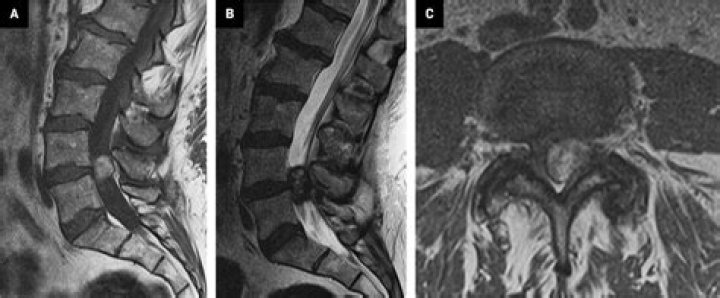

How do you detect a synovial cyst?

How are synovial cysts diagnosed? A synovial cyst is best seen with an MRI. This scan allows your doctor to see inside the spinal column and find any cysts or anything else causing your symptoms. Other imaging tests like an X-ray or ultrasound may also be able to detect the cyst.

What is a T2 hyperintense cyst?